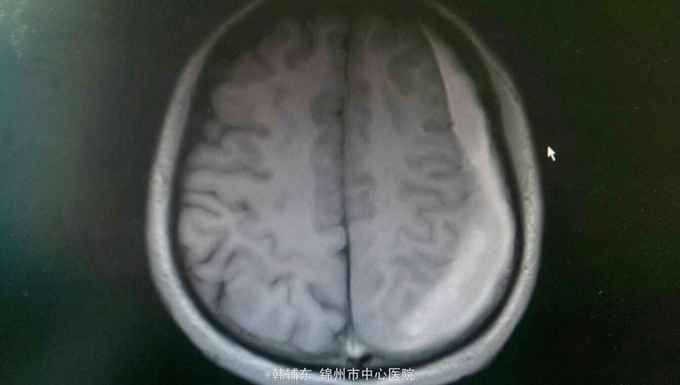

神志清楚,语言流利。神经系统无阳性体征,双侧瞳孔等大正圆直径3.0毫米,光反射灵敏。四肢肌力正常,生理反射存在,病理反射未引出。头部核磁共振显示如下。

诊断:亚急性硬膜下血肿。行血肿钻孔引流术。术后引出陈旧血,患者头痛缓解。

亚急性性硬膜下血肿绝大多数有轻微头外伤史,尤以老年人额前或枕部着力。亚急性颅内压增高症状常于伤后1~3个月后出现如头痛、视物模糊、一侧肢体无力等。精神智力症状表现为记忆力减退、智力迟钝、精神失常等。局灶性症状表现为轻偏瘫、失语等。亚急性或慢性硬膜下血肿MRI的T1和T2均表现为高信号。首选颅骨钻孔冲洗闭式引流术。对于血肿囊壁肥厚伴钙化须行骨瓣开颅清除血肿术。